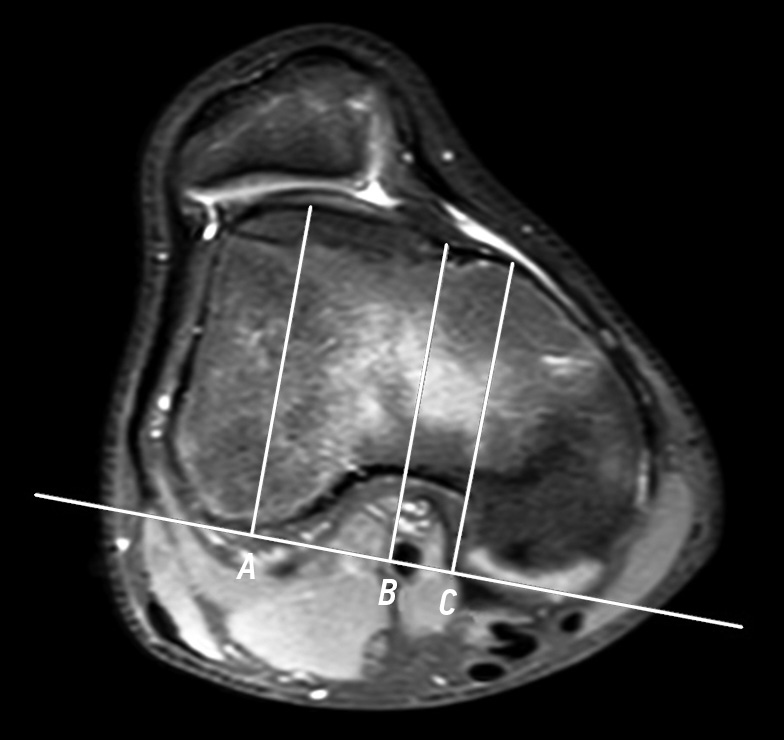

Moreover, MRI was used to determine the presence of free osteochondral bodies and signs of medial patellar margin fracture, and the patellotrochlear index was analyzed. On lateral projection, the height of the patellar articular surface (B) and portion of the trochlear groove articulating with the patella (A) were measured. The ratio А/В × 100% was calculated, with values <12.5% considered normal according to scientific data (Fig. 4) [17].

Fig. 4. Patellotrochlear index on magnetic resonance imaging: a, 16-year-old female with patellar instability. Patellotrochlear index value: 11.4%; b, 15-year-old male with anterior cruciate ligament injury. Patellotrochlear index value: 39.1%. A, length of the trochlear articular surface in contact with the patellar articular surface; B, length of the patellar articular surface (patellar height).